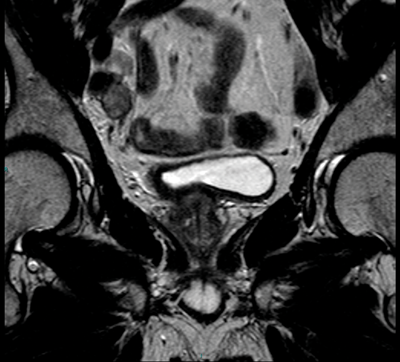

The pelvis and abdomen should be assessed for the presence of lymph nodes. It is often most useful to do this on the coronal view as more of the pelvic lymph nodes are included in this plane and can be easier to visualise (Figure 6).

Figure 6. Coronal T2 image shows right iliac nodes adjacent to the iliac vessels.